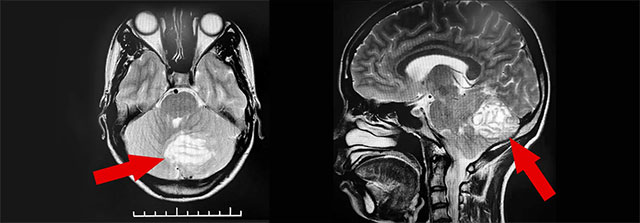

虽然属于相当少见的疾病,但小脑发育不良性神经节细胞瘤较易获得明确诊断。沈教授表示,小脑发育不良性神经节细胞瘤的主要检查方法是磁共振成像(MRI),MRI能清楚显示小脑发育不良性神经节细胞瘤的条纹状或分层状改变表现,即所谓的“虎纹征”——这对小脑发育不良性神经节细胞瘤具有术前定性诊断价值。

▲ MRI检查显示,该小脑肿瘤有明显的“虎纹征”

由于小脑发育不良性神经节细胞瘤非常少见,医院神经外科沈建康教授、侯增欣主任团队对患者进行了有针对性的检查,并结合病情开展了严谨的治疗评估工作。沈教授指出,结合专科查体,患者小脑肿瘤诊断明确,目前患者共济失调症状明显,通过外科手术治疗可缓解患者症状,延缓病情进展。在检查未发现明显手术禁忌症,明确告知手术风险并由家属签字同意后,沈建康教授在侯增欣主任、陈永新博士的协助下,为陶女士开展了肿瘤切除手术。

术中,在蔡司显微镜(双荧光)下可见,肿瘤边界欠清晰,分层叠加生长,呈鱼肉状,质地偏软。生长于小脑部位的肿瘤手术切除难度较大,为了在保护神经组织的同时尽可能多地切除肿瘤,沈教授小心翼翼地将体积约4cm×4cm×2.5cm的肿瘤分成若干小块进行切除,整台手术历时近4小时,手术进程顺利。术后病理诊断示:神经节细胞与胶质细胞混合性肿瘤(WHO I级)。目前,患者仍在术后恢复过程中,身体状况平稳。